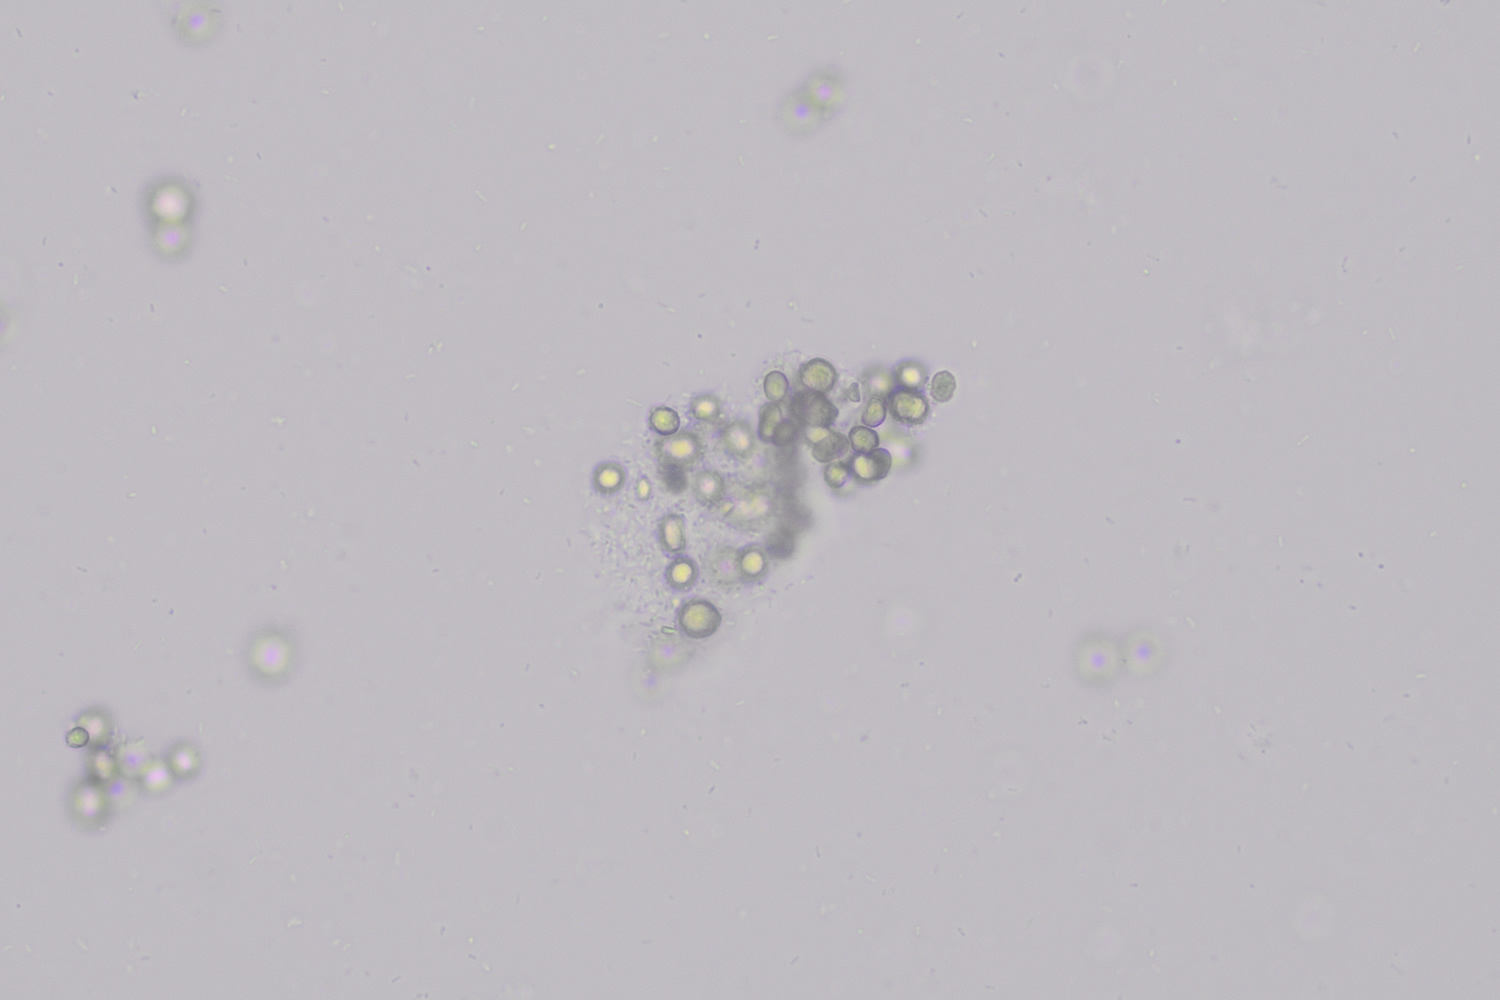

Fat droplets

Fat particles in urine vary in size and are usually round in shape. These droplets consist of cholesterol or triglycerides. When cholesterol is present, they show a characteristic Maltese cross pattern under polarized light.

Fat in the urine can be of biological origin, for example in nephrotic syndrome, where oval fat bodies (oval fat bodies), fatty cylinders (fatty casts) and proteinuria are often found. However, contamination is also possible, for example through the use of oiled catheters or genital creams. In addition, fatty casts can sometimes be observed in severe hematuria, probably from degeneration of erythrocyte membranes.

Finding fat particles is pathological, provided contamination is ruled out.